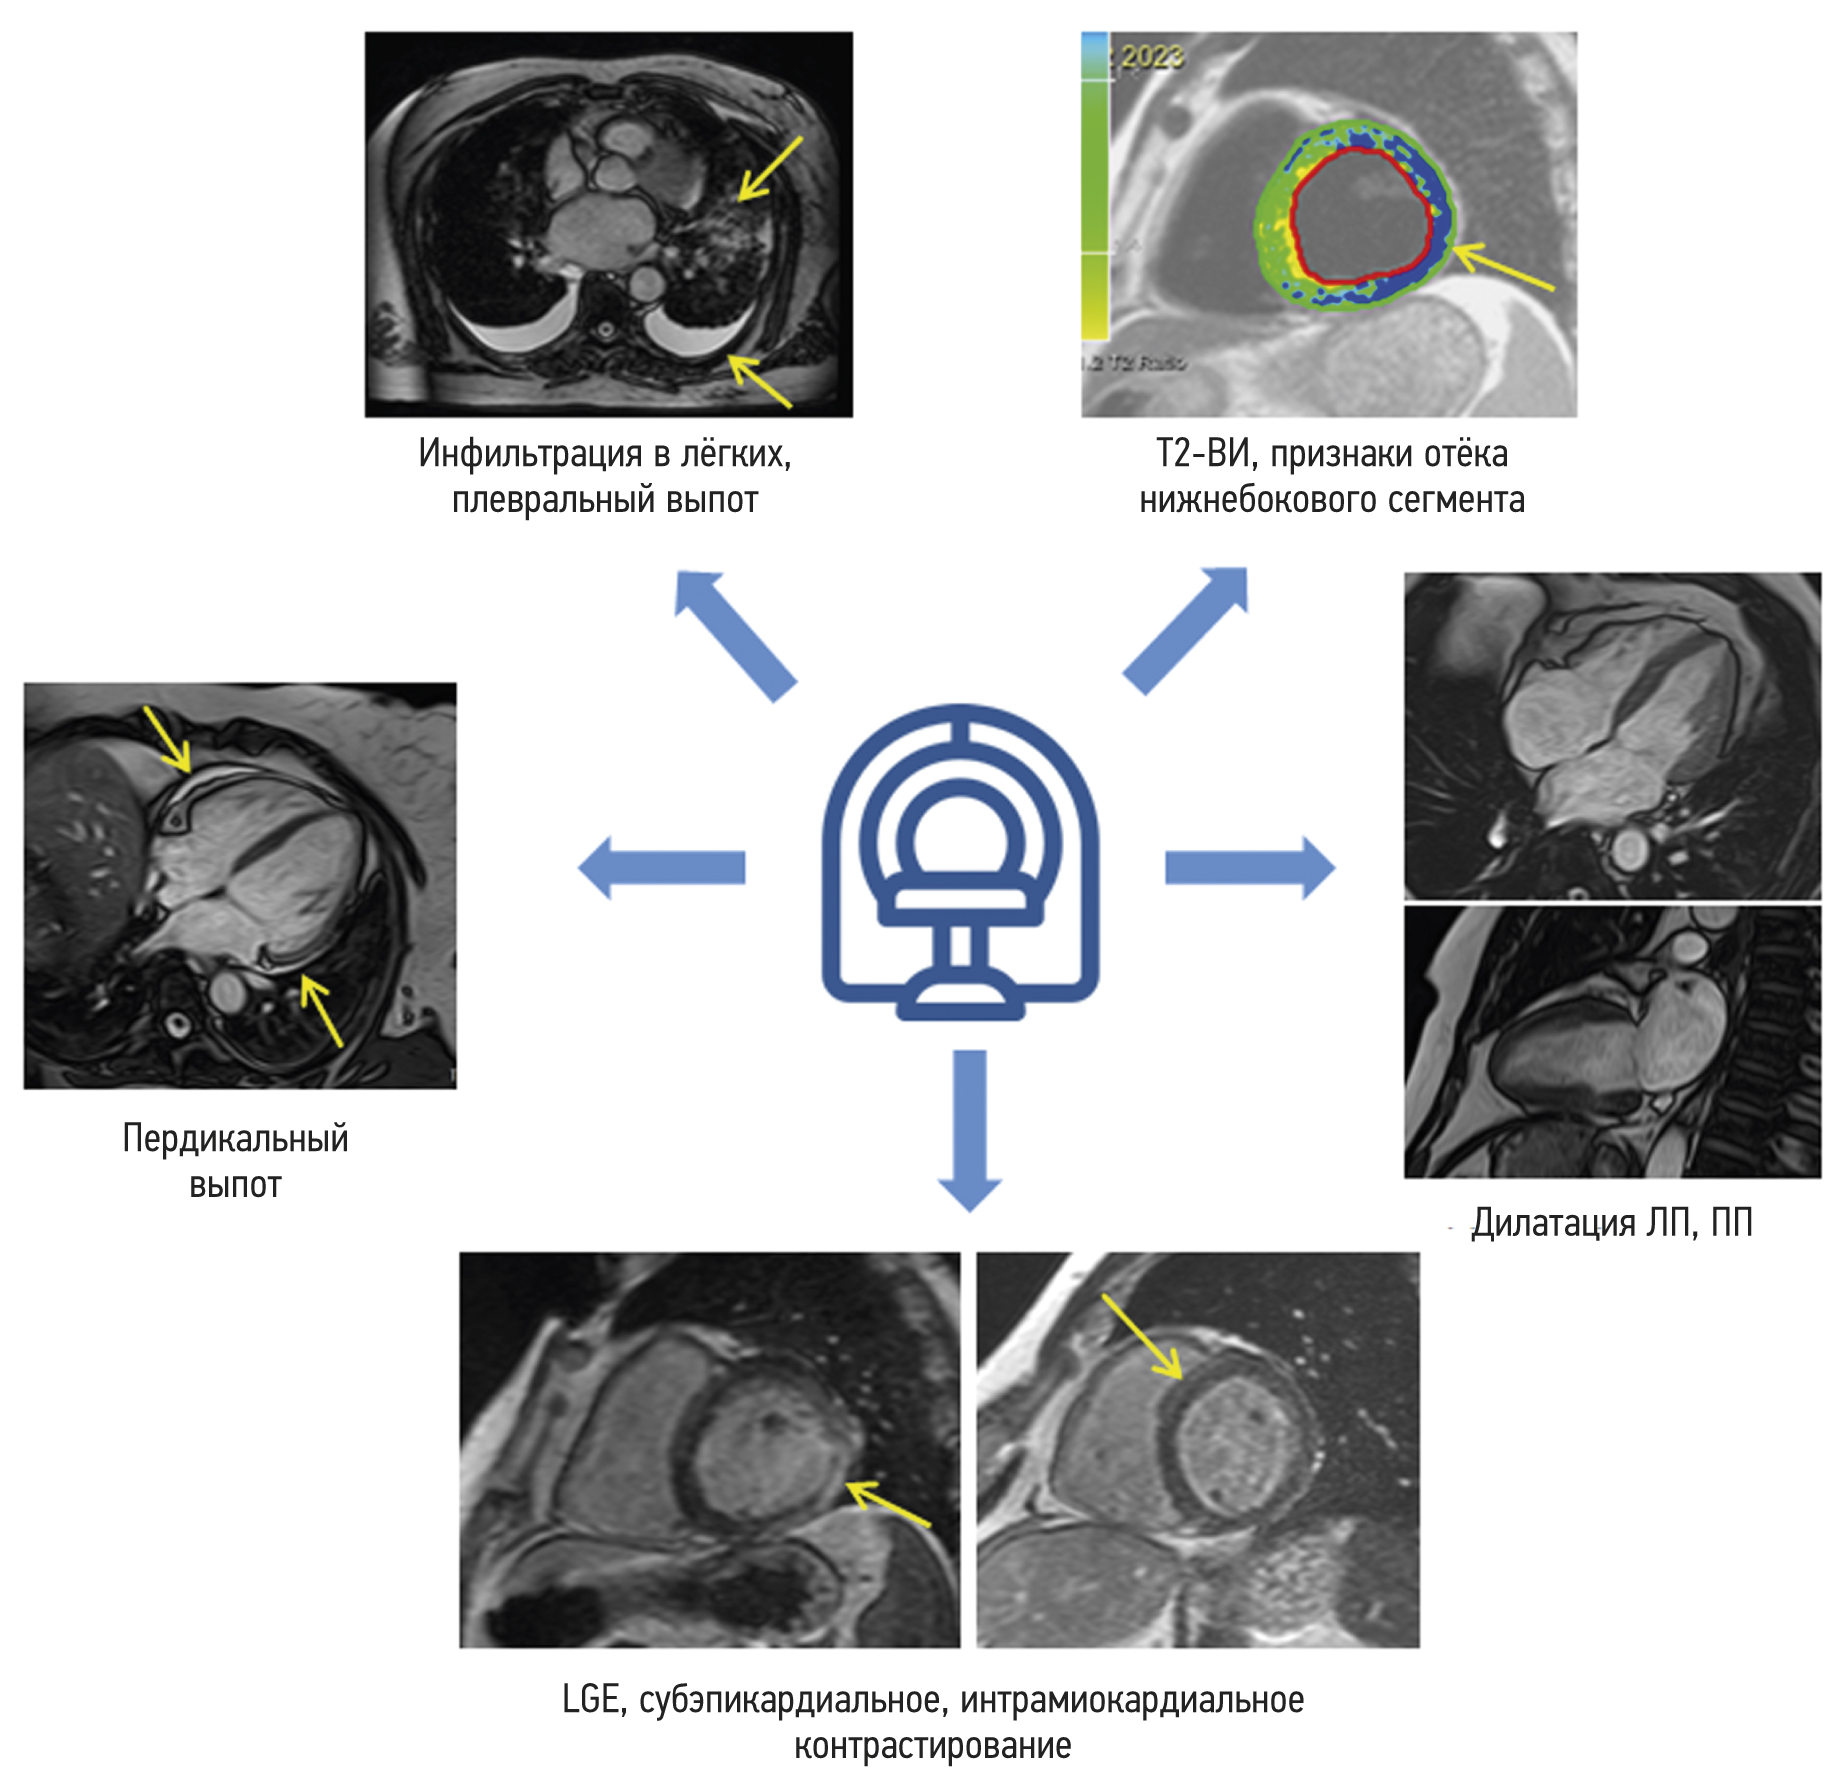

Cardiac magnetic resonance imaging in patients with history of COVID-19

Abstract

BACKGROUND: Myocarditis is among the most common complications arising from coronavirus infection (COVID-19).

AIM: This study aims to find the differences in the patterns of myocardial injury between patients who had COVID-19 and those from the pre-pandemic period, as determined by contrast-enhanced cardiac magnetic resonance imaging.

MATERIALS AND METHODS: The study encompassed a retrospective analysis of 47 patients who underwent contrast-enhanced cardiac magnetic resonance imaging to rule out acute myocarditis. Group 1 comprised 34 patients with a confirmed history of COVID-19 through PCR testing (nasal and/or throat swabs), while Group 2 comprised 13 individuals who underwent contrast-enhanced cardiac magnetic resonance imaging in 2017 prior to the onset of the COVID-19 pandemic. All patients enrolled in the study had clinical manifestation of cardiac injury without signs of coronary artery disease as an underlying cause of condition.

RESULTS: The mean time from the onset of heart symptoms to the administration of contrast-enhanced cardiac magnetic resonance imaging was 166 days. In group 1, a decrease in exercise tolerance was observed in 77% of patients, and 14 (42%), 30 (88%), and 28 (85%) of patients complained of chest pain, shortness of breath, and heart palpitations, respectively. In group 2, four patients (30%) had dyspnea, nine patients (69%) complained of chest pain, and six patients (46%) had heart palpitations and/or feeling of arrhythmia. Myocardial injury in group 1 was more generalized. The third of them had displayed preserved increased pulmonary vascularity and pleural effusion. Within group 1, men had significantly lower left ventricular ejection fraction, lower values of global longitudinal deformation, and higher values of left atrial function compared with the corresponding parameters in women. Differences in women were found only in the number of the affected segments in the left ventricular myocardium.

CONCLUSION: SARS-CoV-2 virus caused extended myocardial injury, affecting a significant number of myocardial segments. Men had more frequent postinflammatory complications, characterized by abnormal function of the left ventricle and left atrium. Obtained results require continuous efforts for further assessment of long-term consequences of previous COVID-19 to the cardiovascular system. In this regard, contrast-enhanced cardiac magnetic resonance imaging may represent a sensitive imaging tool for the assessment of cardiac injury severity.

280-291